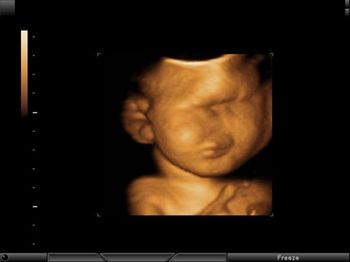

Challenge your diagnostic skills: Can you identify this finding in the fetal chest?

A routine ultrasound exam of a 28-week fetus revealed what looked to be a cystic lesion. The addition of Doppler, however, changed the diagnostic picture.

Challenge your diagnostic skills: Can you identify this anomaly of the fetal face and brain?